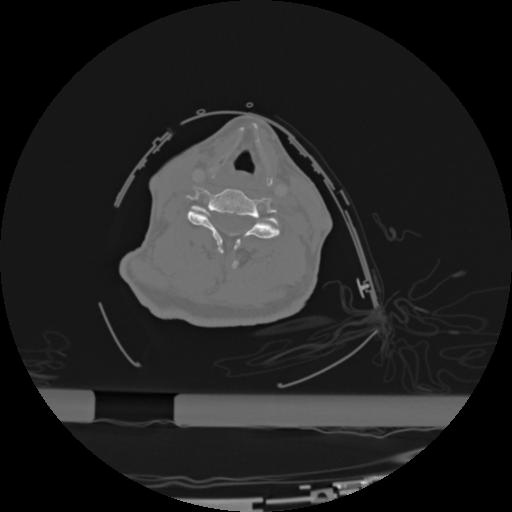

22 ANGIO,CE,Vol,0.5,ANGIO,,